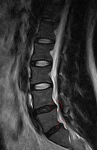

Отпишусь я и тут. Мое заключение МРТ:

Физиологический лордоз поясничного отдела позвоночника сглажен.

Отмечается левосторонний сколиоз с вершиной на уровне L3 и углом 7 градусов.

В телах позвонков Th12-L2 определяются грыжи Шморля.

По передне-боковым поверхностям тел позвонков формируются клювовидные остеофиты, то же самое - по пояничным позвонкам.

Интенсивность MP-сигнала от межпозвоночных дисков L4-L5, L5-S1 и их высота снижены. На уровне L4-S1 визуализируются дорзальные грыжи дисков размером до 3,5 мм.

МРТ-признаки остеохондроза, спондилеза пояснично-крестового отдела позвоночника с наличием грыж Шморля в телах позвонков на уровне Th12-L2, дорзальных грыж дисков на уровне L4-S1. Левосторонний сколиоз I ст.

Снимок также прикладываю.

IDDQD нет, это не бред. Вообще природа допустила в этом отношении какую то оплошность, между диском и самим позвоночным столбом действительно нихрена нет. Да даже МРТ посмотри, что выше приложено, белая линия вдоль позвоночника это и есть пучок нервов (спинной мозг, разветвляющийся в пояснице на более тонкие нервы, так нах. конский хвост), нижние два диска черные, они мертвы, ядро в них застыло и распалось, частично вытекло в сторону спинного мозга, эти вытеки и есть грыжи.